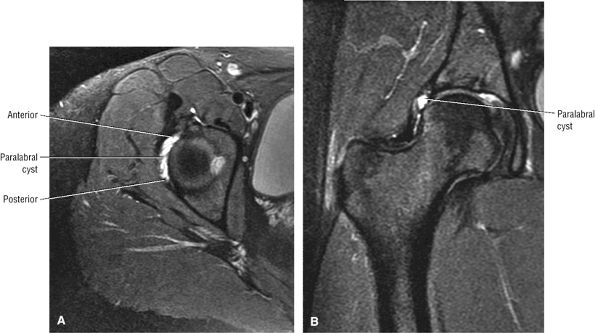

FIGURE 3.29 ● Normal axial anatomy of the hip. (A, B) At this level, the sciatic nerve can be seen exiting the sciatic foramen, deep to the piriformis muscle. Asymmetric enlargement of the piriformis muscle or masses in this region can cause impingement of the sciatic nerve, the so-called piriformis syndrome. (C, D) At this level the transition from the acetabular roof to the top of the femoral head is visualized. The thin arc of dark signal along the lateral margin of the acetabular roof represents the superior margin of the labrum. High signal in the superior labrum can be identified as a labral tear, and accompanying paralabral cysts are commonly identified extending superficial to the labrum. (E, F) The anterior labrum and the posterior labrum on axial images are identified as dark-signal triangles at the lateral margin of the acetabuli. Labral tears present as linear or irregular fluid signal extending through the substance of the labrum, or as expansion of the labrum by fluid signal extending to the surface of the labrum. Fluid signal interposed between the labrum and the acetabulum at the labral attachment indicates labral detachment.(G, H) Tendinosis of the gluteus medius and minimus insertions on the greater trochanter is visualized as thickening and increased signal of the tendons. Trochanteric bursitis can be identified either superficial or deep to the gluteus medius and minimus insertions. (I, J) A fluid collection anteromedial or anterolateral (or both) to the iliopsoas tendon is compatible with iliopsoas bursitis. Occasionally, iliopsoas bursitis may be present adjacent to an anterior labral tear, in which case it may be difficult to distinguish from a paralabral cyst. (K, L) The common hamstring origin on the ischium comprises the biceps femoris and semitendinosus tendons. The common hamstring tendon is a frequent site for tendinosis or partial tears, and the pathology is commonly symmetric.